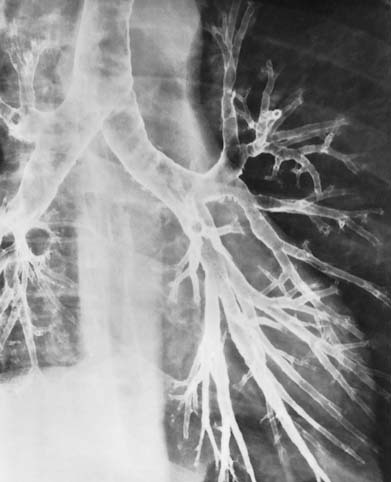

bronchografie. Indien men een patiënt een contrastvloeistof laat inademen, zal deze zich als een film over het slijmvlies van de luchtwegen verspreiden. Door vervolgens een röntgenfoto te maken wordt de bronchiale boom zichtbaar. Men kan zo afsluitingen en afwijkende bronchusvormen op het spoor komen (zie afb. 10.1007/978-90-313-7416-8_8#Fig1 en b). Deze onderzoeksmethode is inmiddels vrijwel overbodig geworden sinds de invoering van de CT-scan;